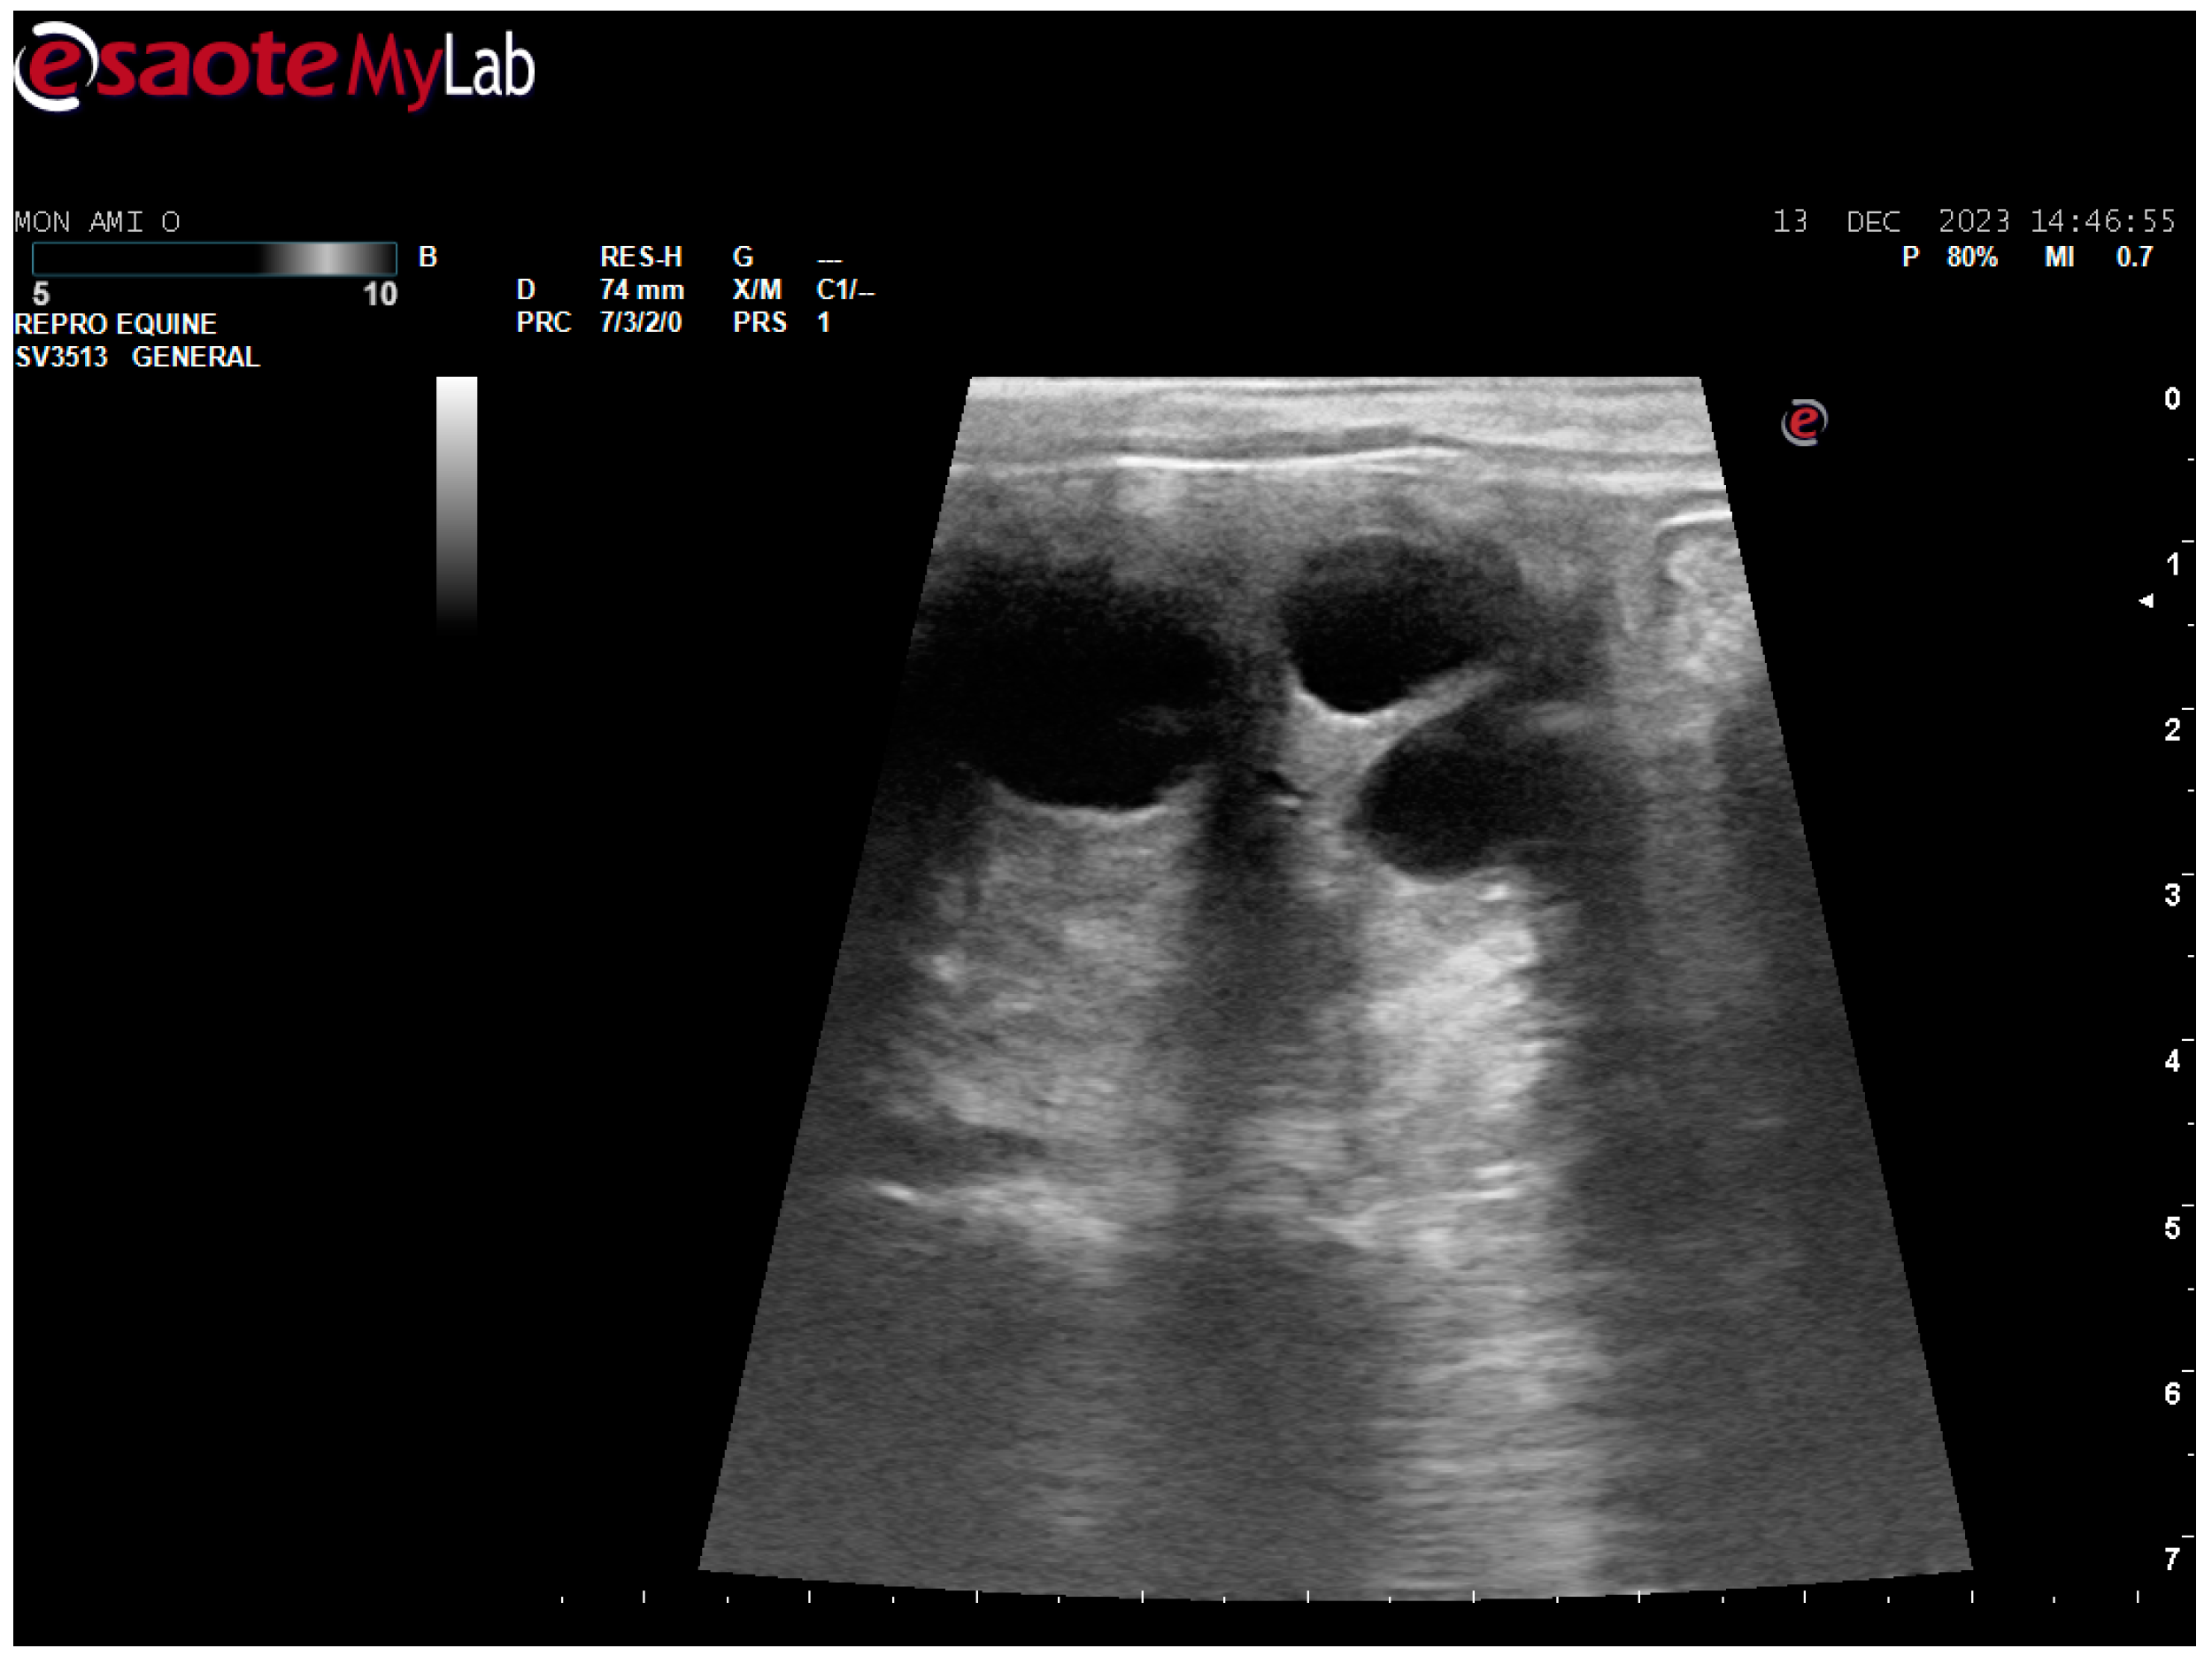

After surgery, the mare’s reproductive system was investigated. Ultrasonographically, slight uterine edema (grade 1 out of 5) and hyperechoic particles (Figure 2), suspected as air in the uterus, were observed. The left ovary was normal in size and echogenicity, present with some 10 to 28.4 mm follicles (Figure 3 and Figure 4). Due to poor perineal conformation, the mare had pneumovagina. Caslic’s vulvoplasty was performed.

Figure 3. Left ovary, present with some >10 mm follicles. Ultrasonographic picture post surgery.

Animals 14 01307 g003